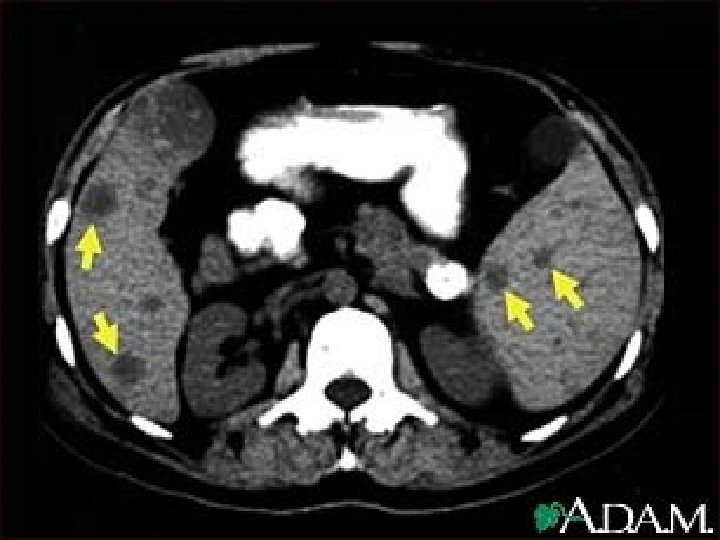

5. CT Modality of choice Used with contrast. Findings : 1. 2. 3. 4. Lacerations : irregular hypodense area with no enhancement. Sub-capsular hematoma : regular shape , cresentric. Intraparenchymal hematoma. Fragmentation with autosplenictomy.